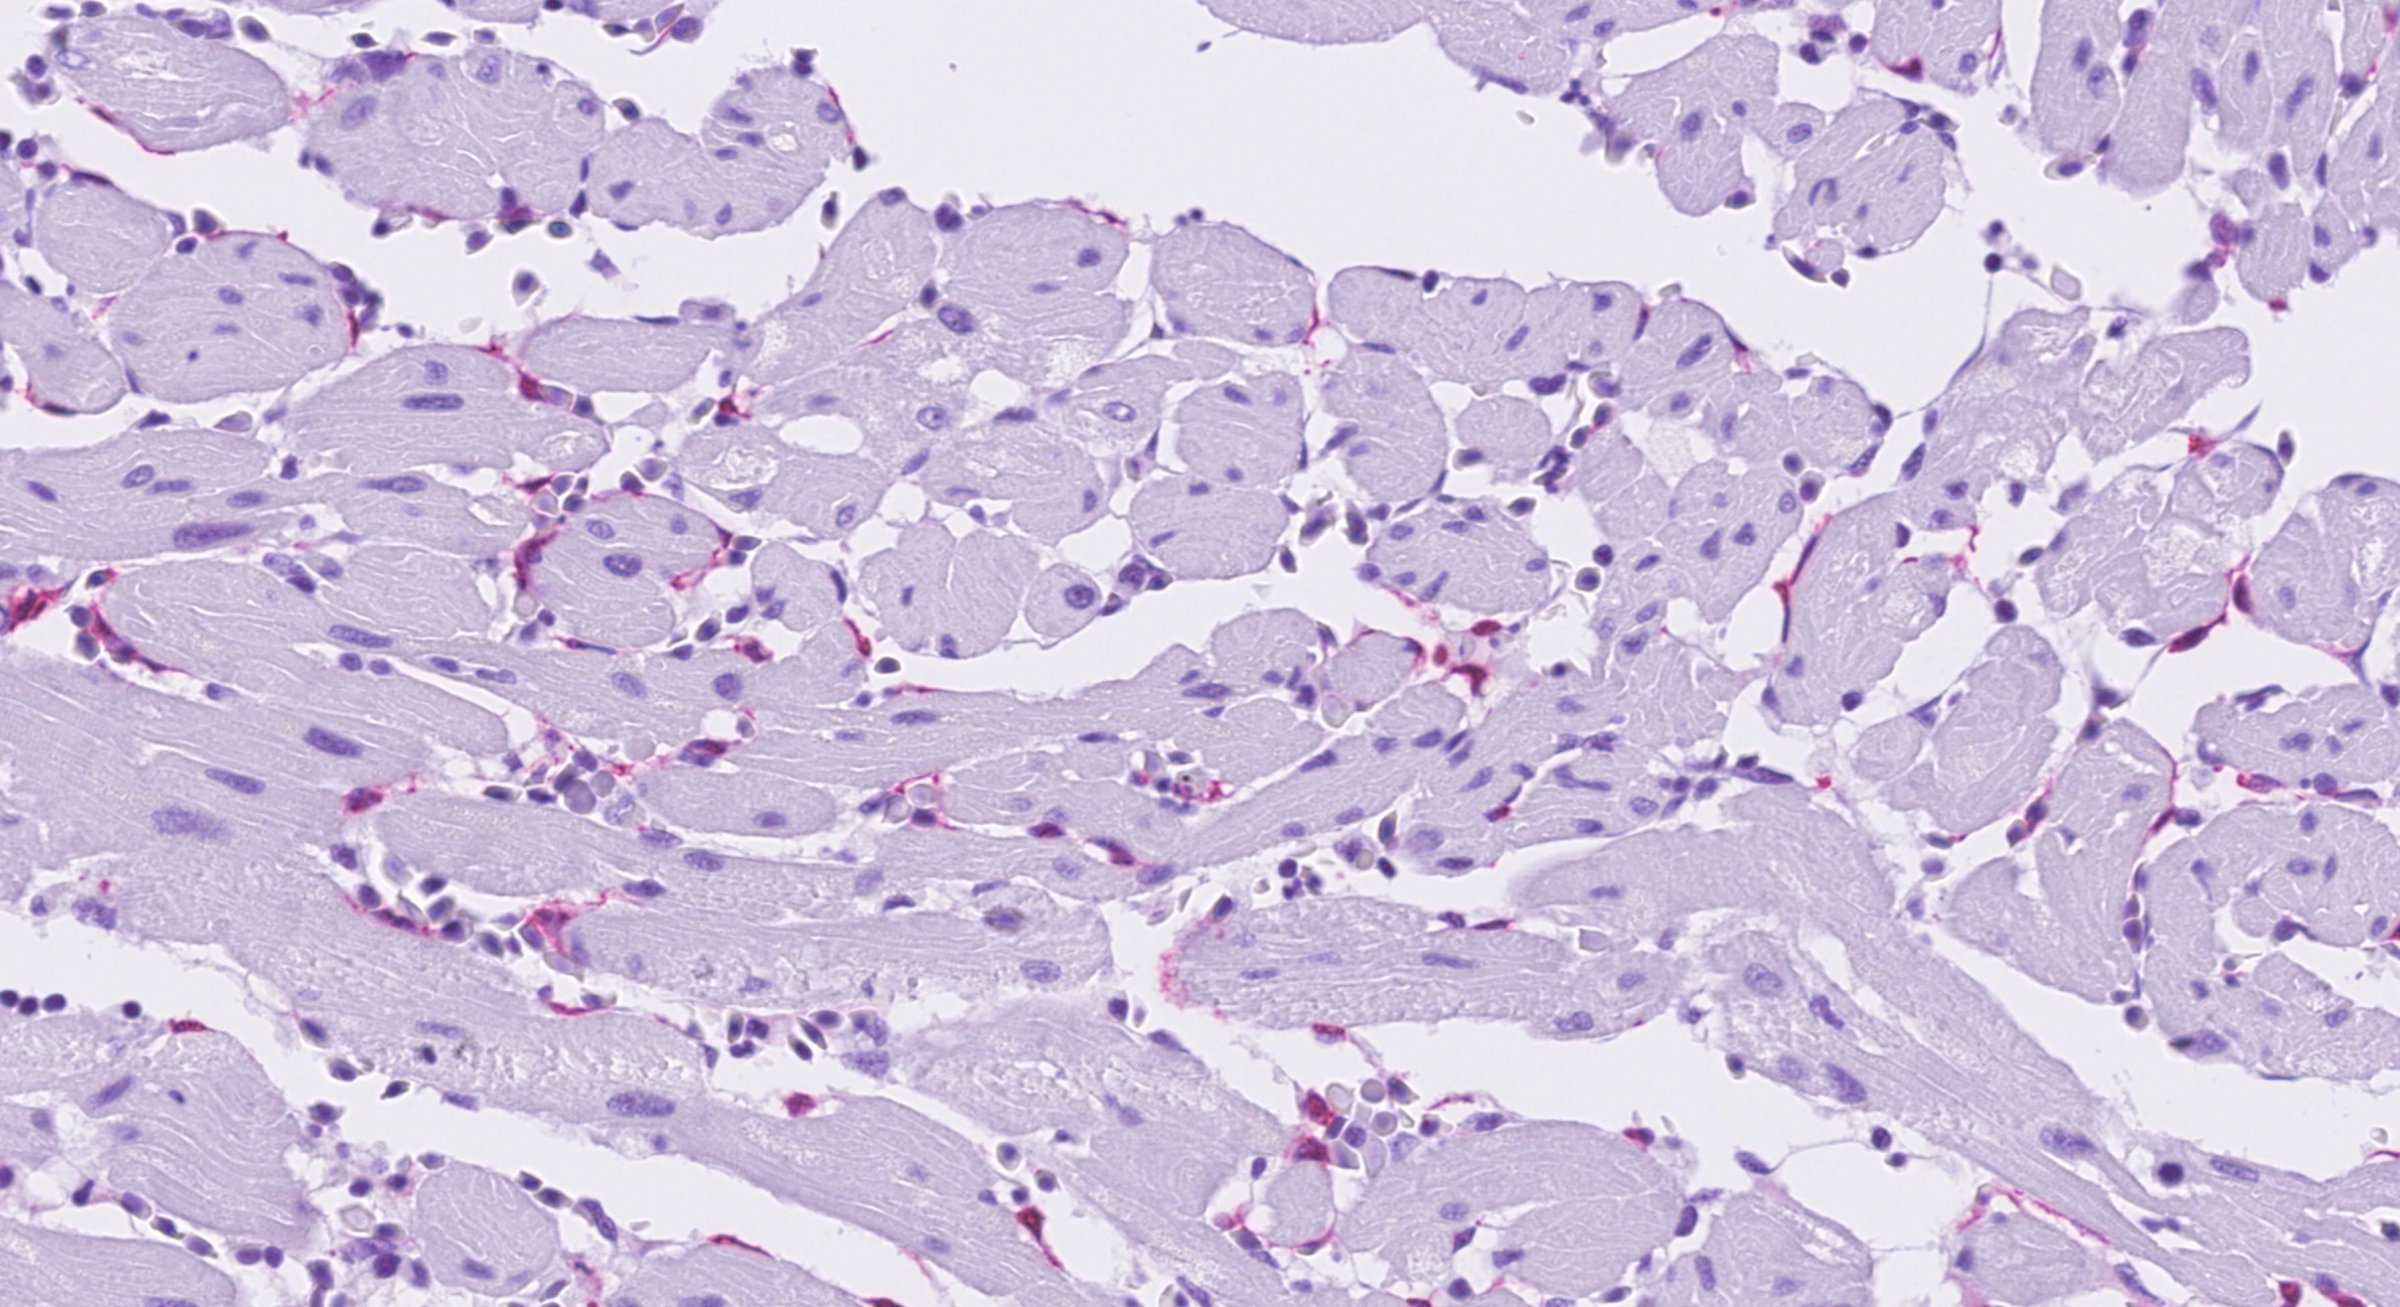

Prøver til histopatologisk undersøkelse sendes til Veterinærinstituttets laboratorium i Harstad for prosessering og digital scanning. Avlesningen skjer digitalt av vårt histopatologiske team.